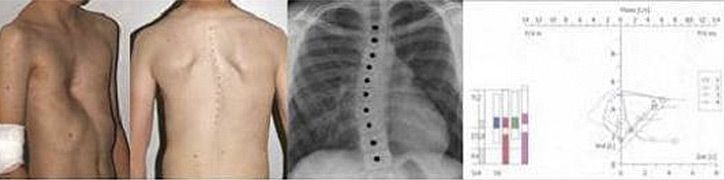

- Falsche Körperhaltung, Entwicklung einer Wirbelsäulenverkrümmung (Skoliose)

- Vermessung und Fotodokumentation des Befundes

- Röntgenbild des Brustkorbes in 2 Ebenen

- Lungenfunktionstest unter Belastung (Spiroergometrie)